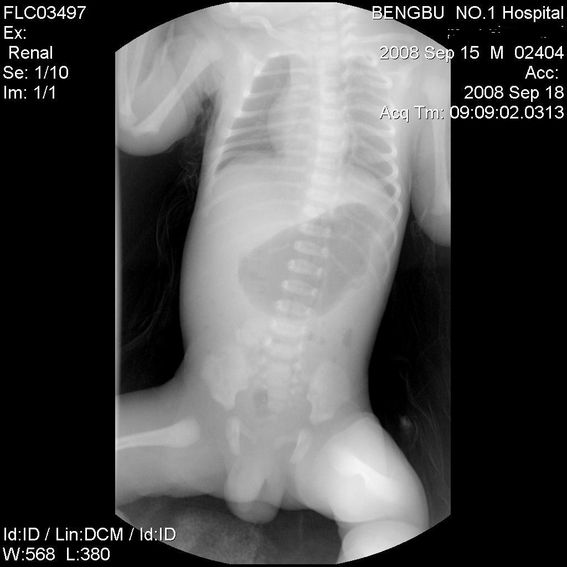

标题: PED1734:男,3天,以呕吐来诊。

十二指肠降部钡流不能顺利通过,胃及十二指肠球扩张。

考虑----十二指肠降部狭窄-----〔但这几个片子狭窄未能清楚显示,无法判断分型-----膜性或管状〕

考虑----十二指肠降部狭窄

十二指肠降部狭窄(可能为环状胰腺)。

十二指肠降部钡流不能顺利通过,胃及十二指肠球扩张,符合十二指肠降部狭窄

符合十二指肠降部狭窄或扭转不良.

考虑十二指肠降部狭窄.